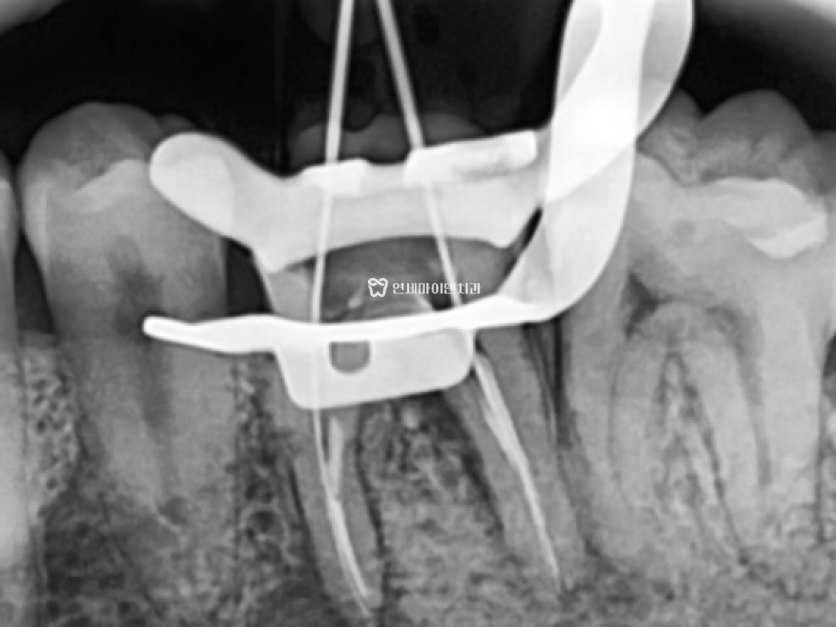

우선 기존의 크라운을 제거한 뒤

치아 내부 상태를 면밀하게 확인했고,

미세현미경 검사 결과 크랙이 발견되지 않았습니다.

뿌리 아래쪽부터 시작된 금이라면 위쪽에서 보이지 않을 수 있지만

크랙이 확인되지 않았기 때문에

원칙적인 치료인 재신경치료를 시도하였습니다.

기존 신경치료 재료를 꼼꼼하게 제거한 뒤

신경관을 깨끗하게 청소하고 약물을 다시 채워넣었습니다.